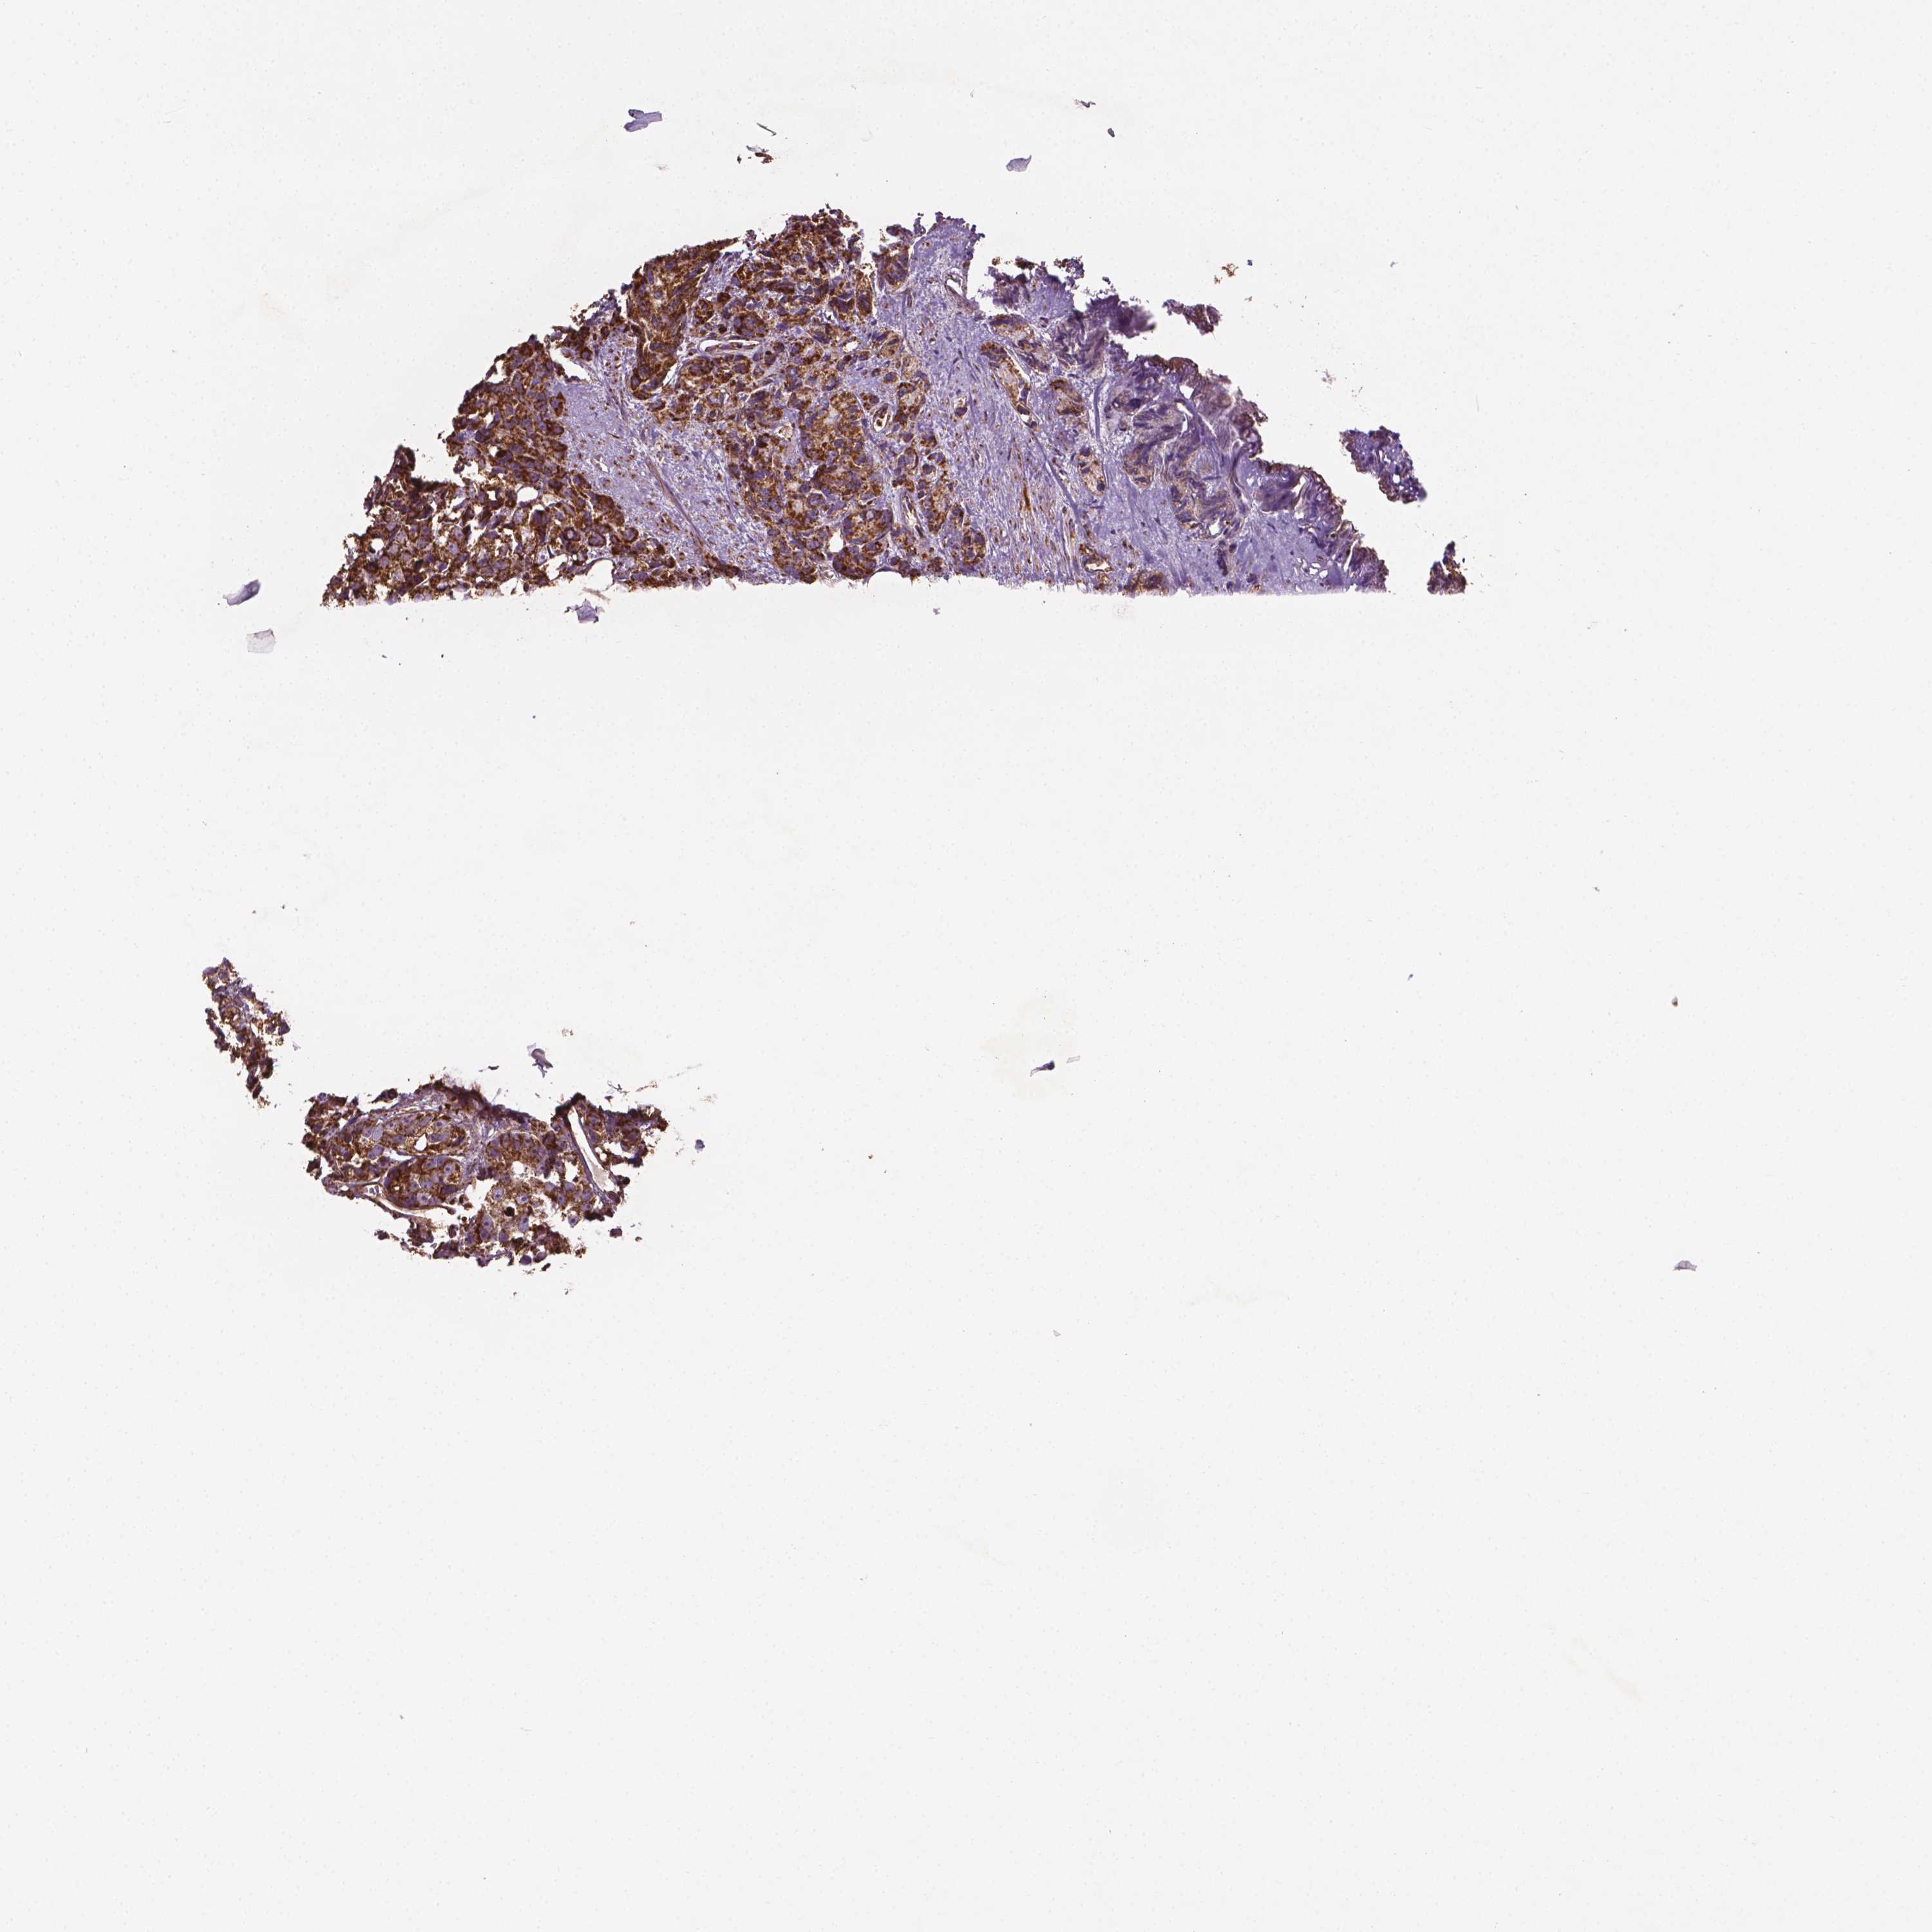

PROSTATE CANCER - Protein expressioni

A mouse-over function shows sample information and annotation data. Click on an image to view it in a full screen mode. Samples can be filtered based on level of antibody staining by selecting one or several of the following categories: high, medium, low and not detected. The assay and annotation is described here.

Antibody stainingi

Antibody staining in the annotated cell types in the current human tissue is reported as not detected, low, medium, or high, based on conventional immunohistochemistry profiling in selected tissues. This score is based on the combination of the staining intensity and fraction of stained cells.

Each image is clickable and will lead to virtual microscopy that enables deeper exploration of all samples and also displays staining intensity scores, fraction scores and subcellular localization as well as patient and tissue information for each sample.

Antibody HPA071530

Staining

High

Medium

Low

Not detected

Intensity

Strong

Moderate

Weak

Negative

Quantity

>75%

75%-25%

<25%

None

Location

Nuclear

Cytoplasmic/membranous

Cytoplasmic/membranous,nuclear

Adenocarcinoma, High grade

Adenocarcinoma, NOS

Adenocarcinoma, Low grade